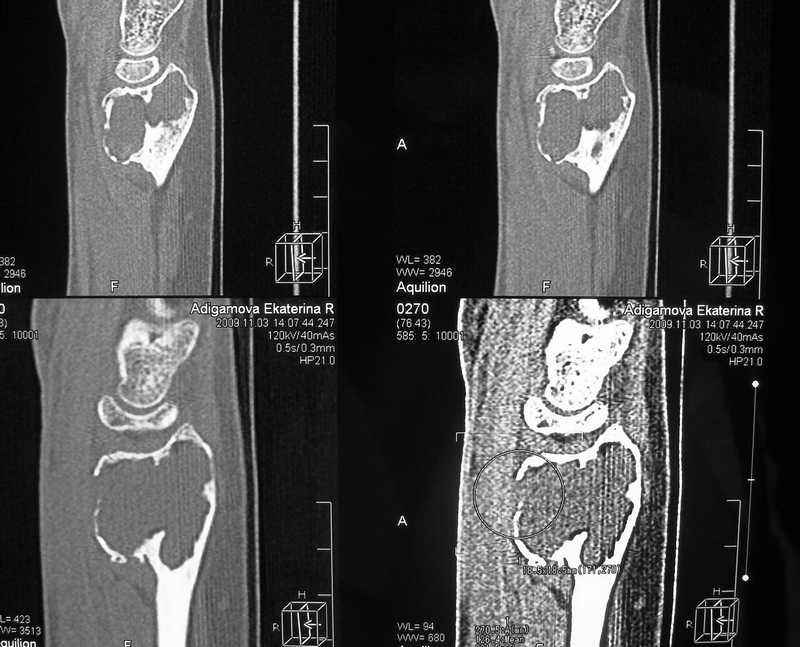

ОБК дистального эпифиза левой лучевой кости

Здравствуйте, уважаемые коллеги! На приём обратилась молодая женщина 28 лет с жалобами на наличие образования в области левого лучезапястного сустава.

Болевой синдром умеренный, "ночных" болей нет. Полтора года назад - патологический перелом дистального эпиметафмза левой лучевой кости. В Областном онкодиспансере выполнена открытая биопсия патологического очага.

Морфологическое заключение: остеобластокластома без признаков малигнизации.